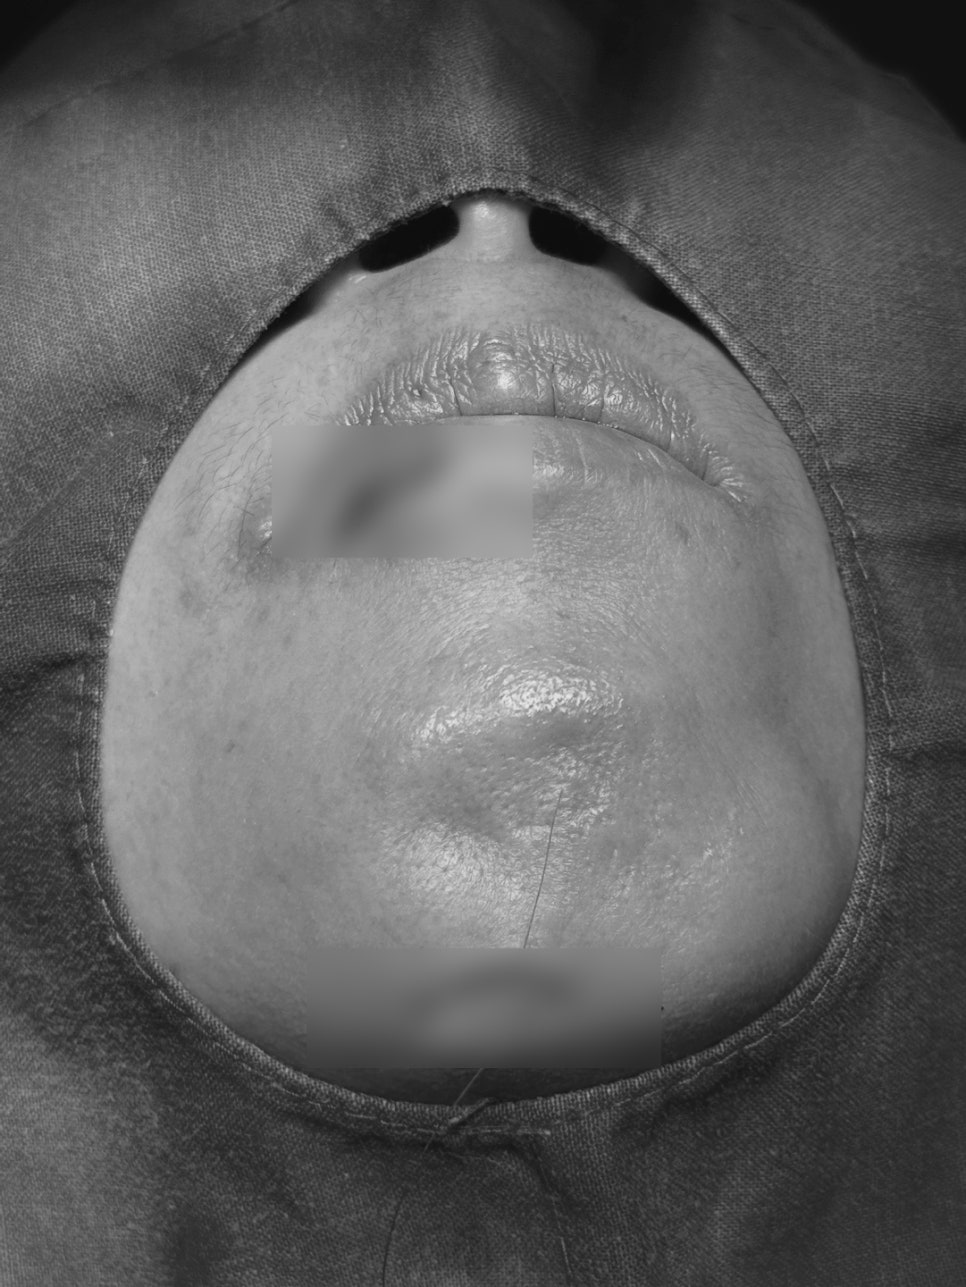

Recently, a woman in her 50s visited Seoul Orbit Dental Hospital

after falling due to dizziness while eating,

sustaining a deep tear to her lip and gums,

with her front teeth pushed inward.

Although it looked like a simple wound, CT imaging revealed

an alveolar bone fracture around the front teeth and tooth displacement.

For this patient as well,

the panoramic X-ray and CT scan clearly confirmed

an alveolar bone fracture around the two front teeth and tooth displacement.

Immediate professional stabilization was needed.